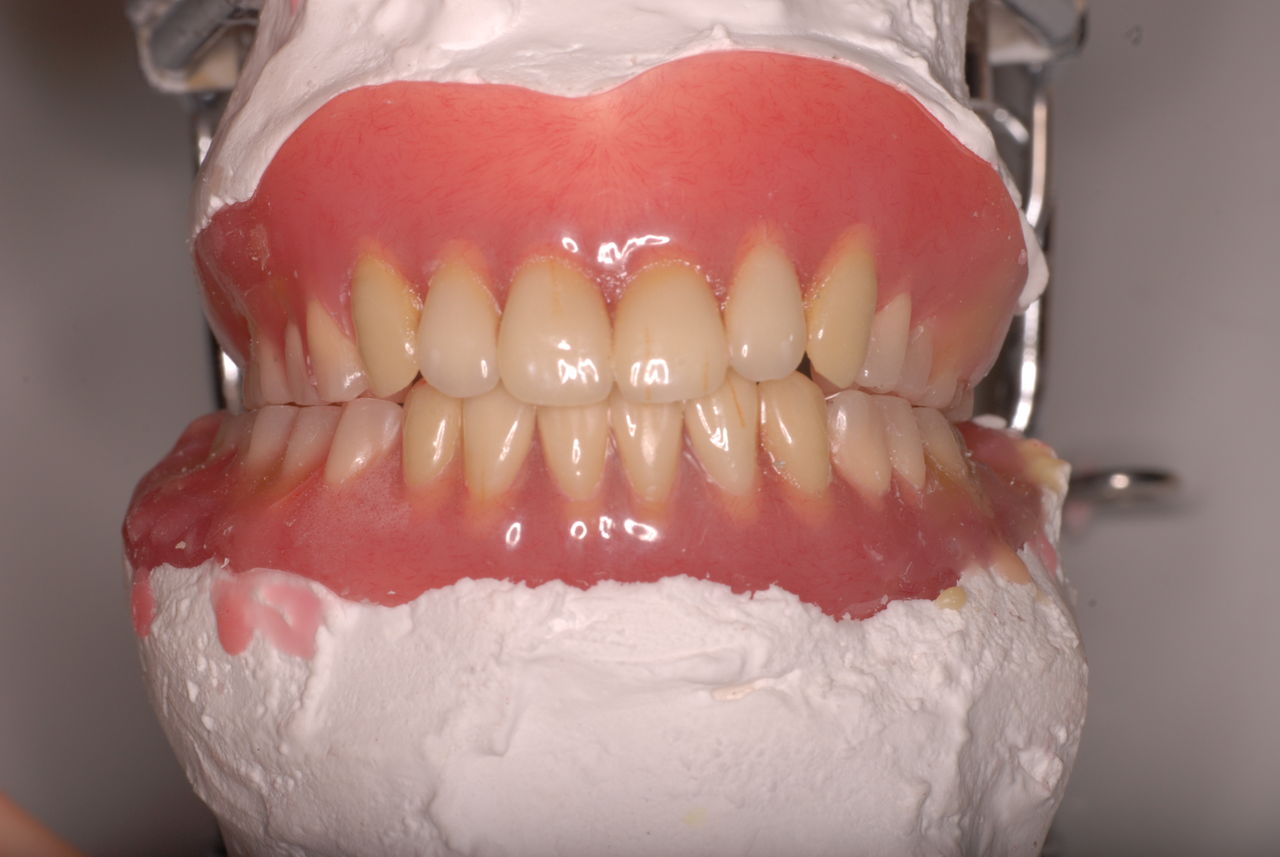

70代の患者ですが上の歯は残根一つ全て歯は無し。

下顎、殆ど歯はなく歯周病で抜けそうな歯と虫歯だらけの歯、適合の悪い銀歯が入っていてそれも虫歯と歯周病で危ない状態でした。入れ歯は下の入れ歯は入れたことがないようです。(ため息)痛くて入れたことがないそうです。

クラスプという歯を取り囲むワイヤ−が折れたりしてまともに機能していません。構造的な問題もあるのでしょうがヒビも目立ちます。殆ど使わずに御蔵入りとなったようです。値段の問題からかそうではないか判然としませんが、入れ歯というのは残りの歯や歯周病の治療がある程度完了してからでないと良い機能的な入れ歯などはできません。せいぜい治療中用の簡素な物を作成して歯や歯茎の病気が治るのを待ちながら様子をみるしかないのです。

一旦歯が悪くなり病気になり崩壊している場合は、かなりの時間と費用がかかるのはしかたないことです。物ですから全て価格統一して好いものが出来るとは思えません。大学や講習会で習った理想的な入れ歯は自由診療以外では無理なことを理解していただくしかないのです。